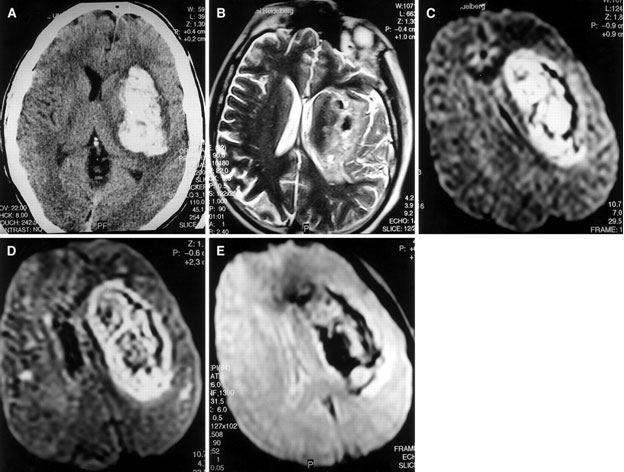

- MRI and CT scan: Your physician may order MRI or CT scan or both.